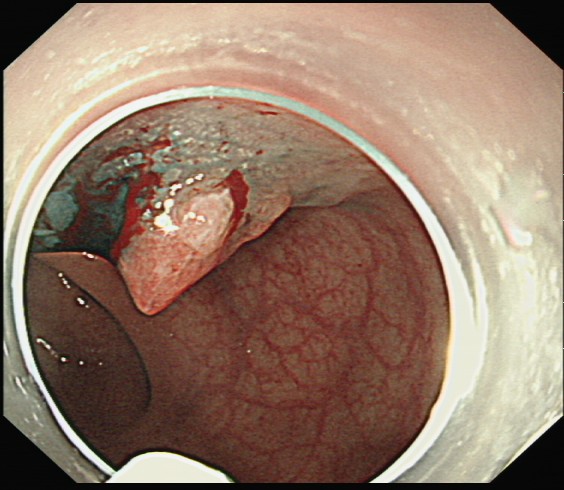

微创“拆弹”:内镜下的精准手术——ESD

在省人民医院专科联盟指导下ESD手术顺利完成,为什么“完整剥离”如此重要? 因为只有这样,才能将病灶连根拔起,并获取完整的病理标本,为后续的诊断和治疗提供最可靠的依据。也避免了外科开腹手术。

黄女士成功接受了ESD手术。术后病理分析证实了术前的判断:绒毛状管状腺瘤,局灶高级别上皮内瘤变。

高级别上皮内瘤变:这是一个关键的医学术语,通俗讲就是“癌前病变”的最高阶段,或者可以理解为“最早期的癌”,细胞已经出现了恶性的特征,但还没有获得强大的侵袭和转移能力。

正是因为发现得极其及时,黄女士的病情被扼杀在摇篮里。通过ESD这一微创手术,她不仅完整切除了癌变组织,更幸运地保住了肛门和直肠的完整功能,避免了外科开腹手术带来的巨大创伤、更长的恢复期以及可能需要的肠道改道(造口)。术后几天,黄女士便顺利出院,回归正常生活。